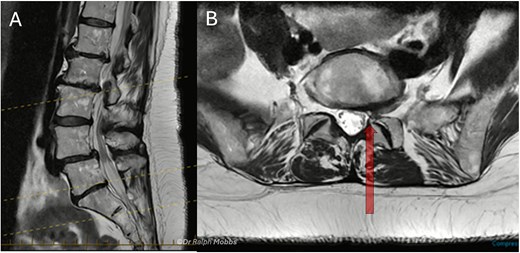

A 60-year-old female presented with a 3-year history of chronic left-sided S1 radiculopathy. MRI demonstrated stenosis of the left lateral recess at L5–S1, with no imaging indication of an underlying nerve root anomaly (Fig. 4).

Case 2 mid-sagittal (A) and axial (B) T2-weighted MRI at L5/S1 with lateral recess stenosis (arrow).